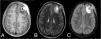

Un niño de 11 años presentó aumento de volumen en la región frontal izquierda, sin déficit neurológico ni síntomas sistémicos. La tomografía y la resonancia magnética revelaron una lesión osteolítica agresiva con edema perilesional y extensión intracraneal.

An 11-year-old boy presented with increased volume in the left frontal region, without neurological deficit or systemic symptoms. CT and MRI revealed an aggressive osteolytic lesion with perilesional edema and intracranial extension.